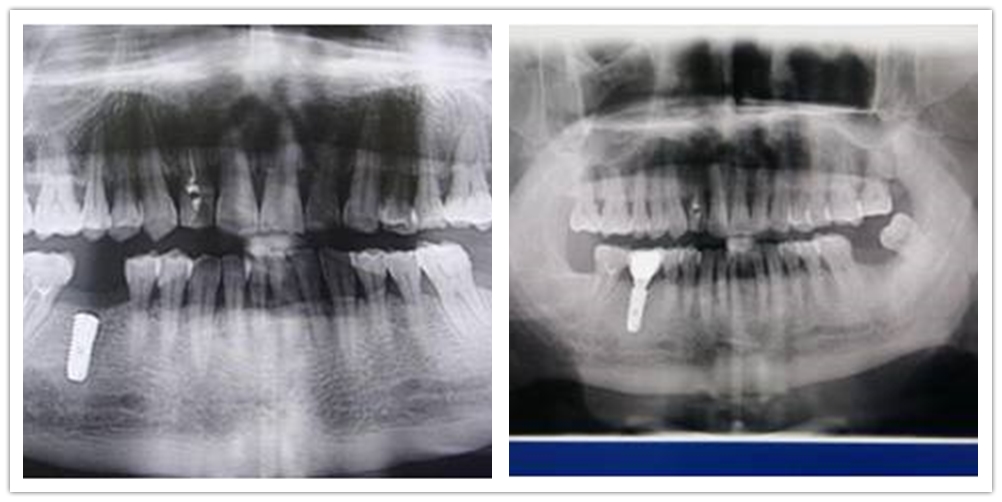

三、口腔修复:开展全瓷牙、烤瓷牙、瓷贴面、嵌体、桩核冠修复治疗、种植牙、局部活动义齿、全口义齿、咬合重建、精密附着体等修复技术,使我院义齿的功能性、美容性修复工作取得了满意的临床效果。精密附着体修复技术、种植牙技术的开展,满足了不同层次的口腔医疗需求,使修复治疗工作提到一个新层次。

种植牙术前术后